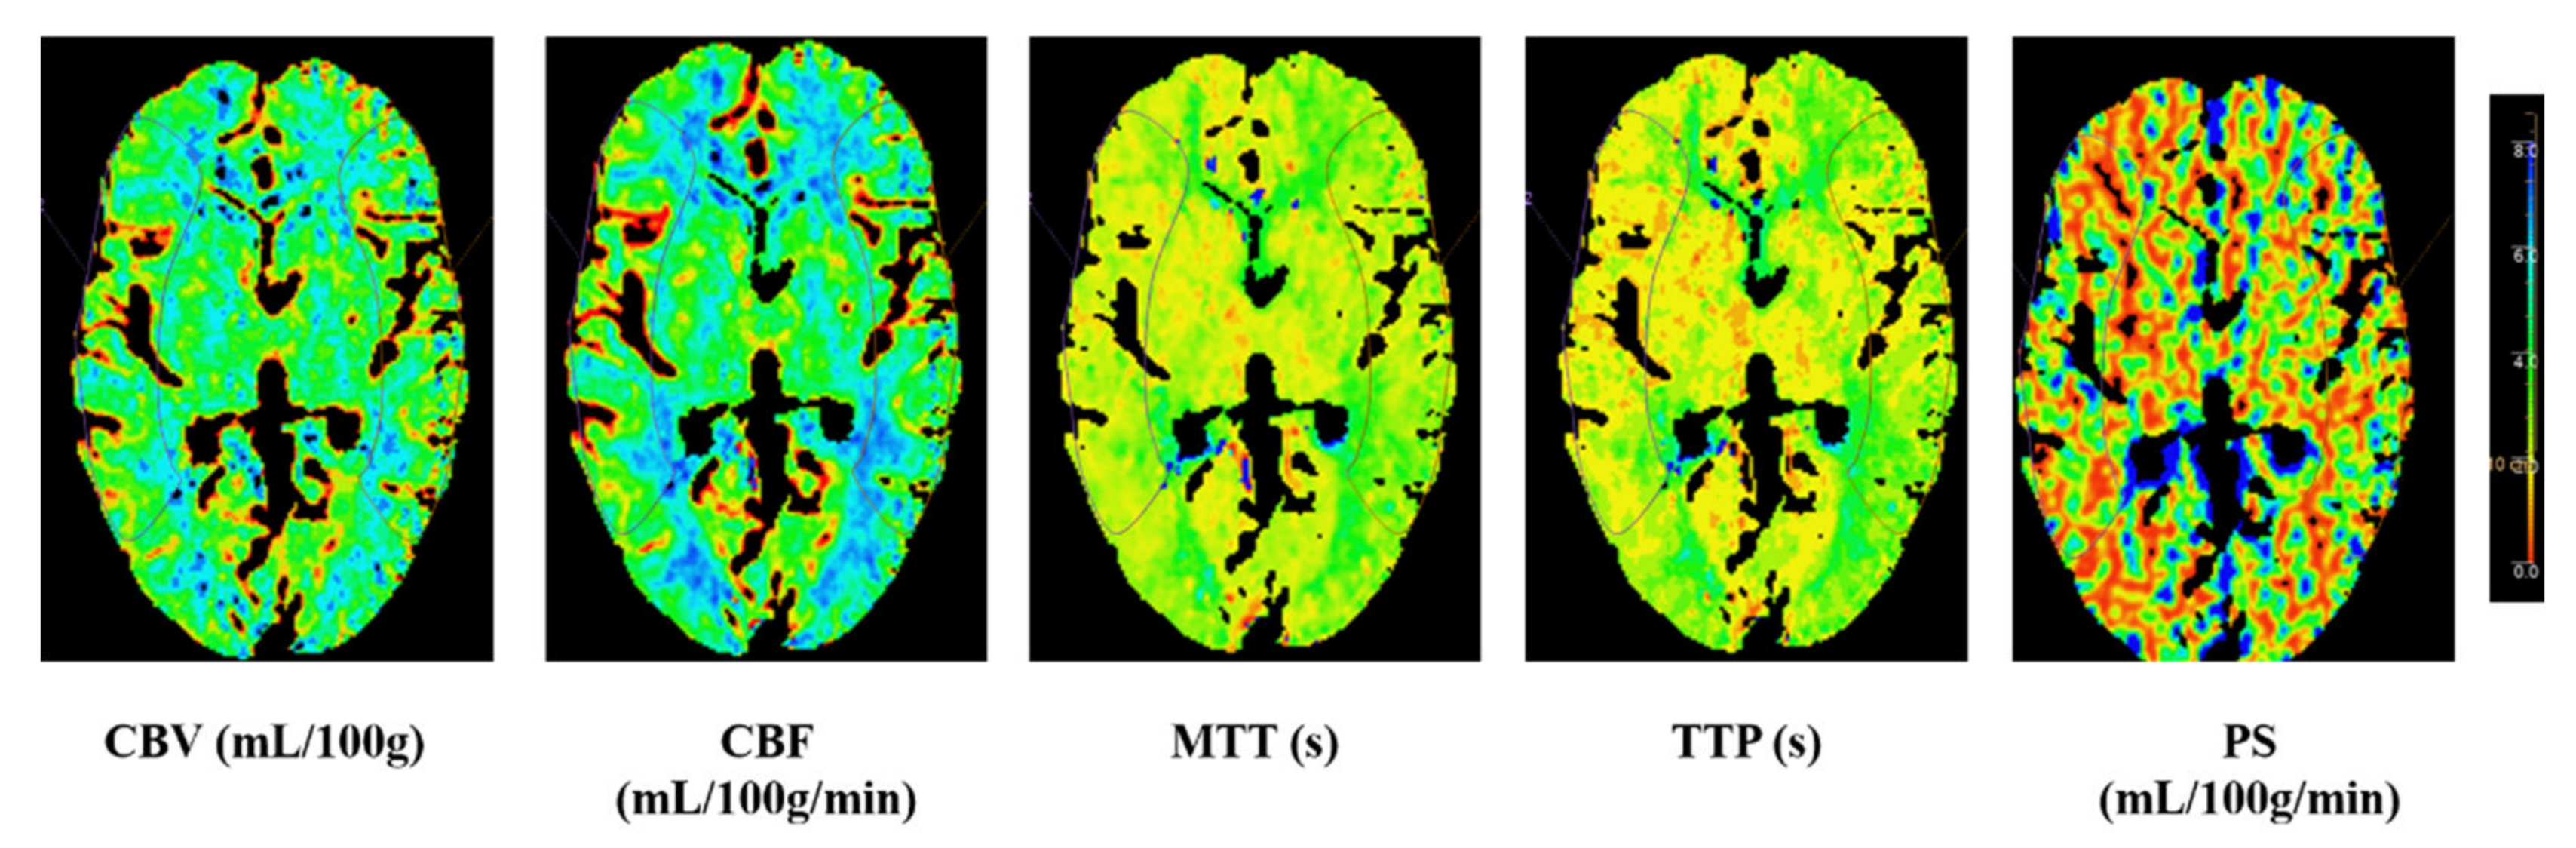

CTP images were transferred to a workstation (IntelliSpace Portal system, Philips Healthcare, Amsterdam, The Netherlands) to generate perfusion parameter maps of the cerebral blood flow (CBF), cerebral blood volume (CBV), time to peak (TTP), mean transit time (MTT) and permeability surface (PS). Regions of interest (ROI) were drawn on CTP source images (average images calculated from all phases that could offer accurate anatomical references) and transferred to corresponding parametric maps. Absolute values of CBF, CBV, TTP, MTT and PS in bilateral MCA territories were measured at the basal ganglia level by drawing symmetrical ROI in the two hemispheres on perfusion maps. Relative (r) CTP parameters (rCBF, rCBV, rTTP, rMTT and rPS) were calculated as the ratio of the value on the contralateral side to the ipsilateral side for each ROI as shown in Figure 1.

Figure 1.

Illustrative image at the basal ganglia level by drawing symmetrical region of interest (ROI) in the two hemispheres on perfusion maps. CBV: cerebral blood volume; CBF: cerebral blood flow; MTT: mean transit time; TTP: time to peak; PS: permeability surface.